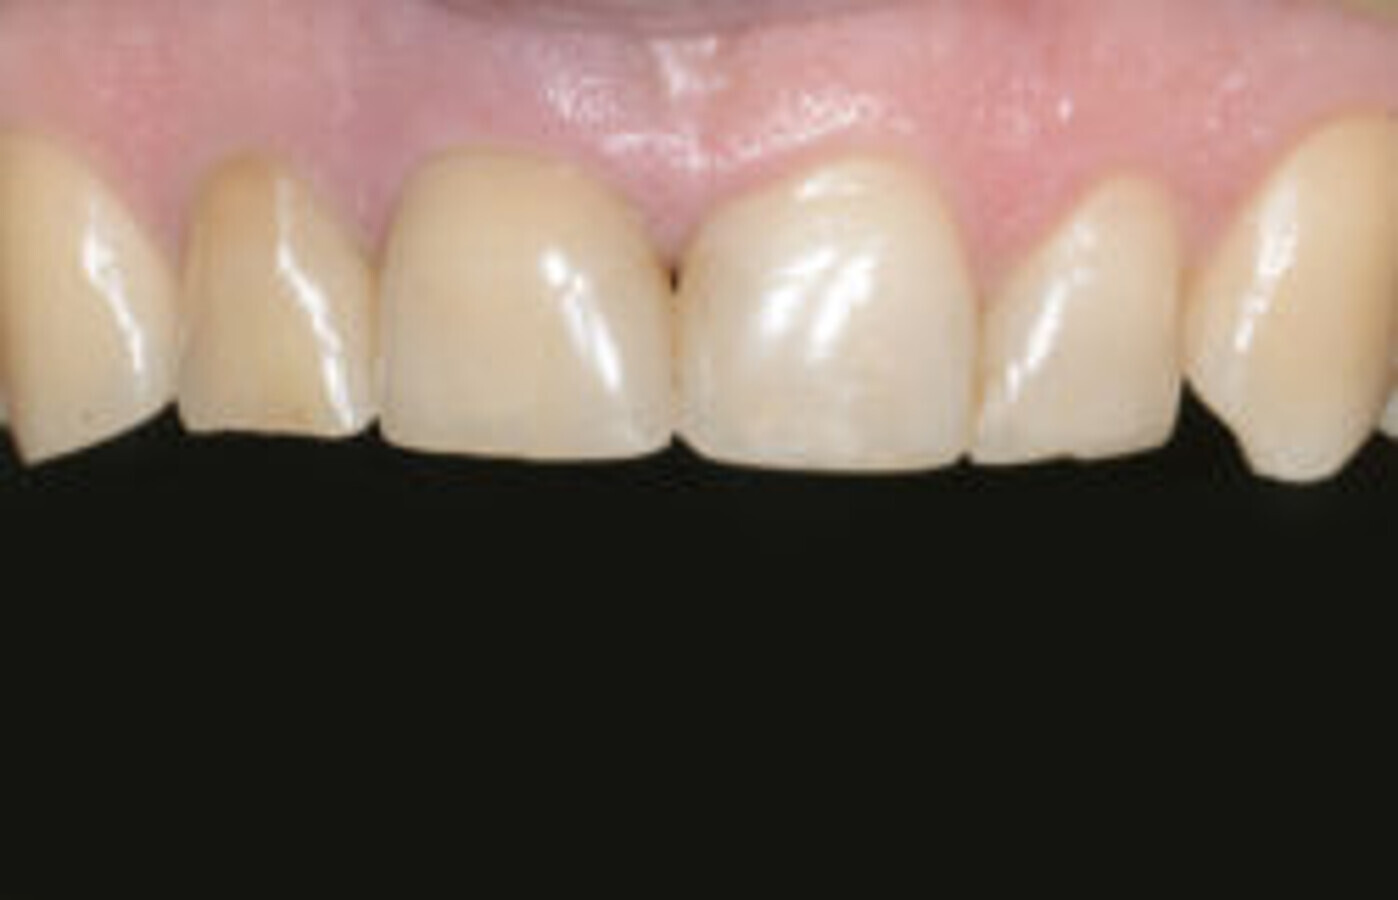

图16. Ankyos种植体的牙床下植入。将螺丝固位的IPSe.max牙冠安装在Atlantis基台上(无功能修复)。

图18. 种植体周围的软组织适应良好。此外,在#12(根管治疗后)安装了陶瓷冠,#21和#22安装了陶瓷贴面。三年的随访显示软、硬组织无殊。

使用simplant guide,精准、安全地行骨下种植(图12-15)。Atlantic 基台上的螺丝固定全瓷冠(非功能性修复)在种植后即被安装(图16)。后续CBCT显示,simplant软件完美定位了种植体(图17)。

治疗非常成功,最终结果患者十分满意。三年后复诊可见种植体周软组织适应性良好(图18)。此外,#12根管治疗后安装了陶瓷冠,#21和#22安装了陶瓷贴面。